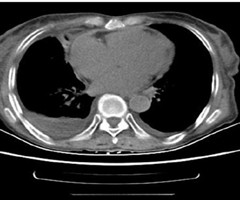

不同类型心源性肺水肿病人血浆BNP水平变化

摘要目的:探讨心源性肺水肿CT表现与血浆脑钠肽(BNP)水平的变化。方法:选取2022年9月—2023年9月在临汾市人民医院心内科及急诊就诊的心源性肺水肿病人213例,全部病人均行胸部CT平扫,部分病人行血浆BNP及N末端脑钠肽前体(NT-...

PET-CT诊断缩窄性心包炎1例并文献复习

摘要缩窄性心包炎的右心衰竭临床表现无特异性,诊断常基于心包增厚或钙化的影像学依据,在常规检查未发现心包增厚或钙化 时易误诊。报道1例反复心脏彩超及CT未发现心包增厚,经正电子发射计算机断层显像(PET-CT)发现心包炎症显著,且心包增 厚,...